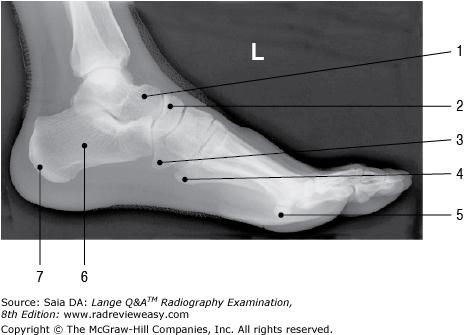

Which of the labeled bones in Figure 6–14 identifies the tarsal navicular?

Number 6

What does the number 8 in Figure 6–14 identify?

Medial malleolus